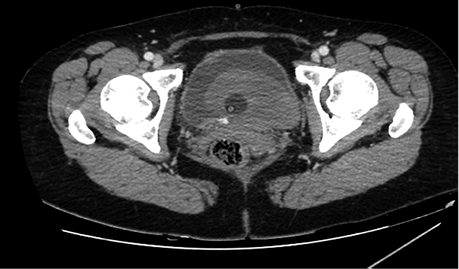

Figure 3. Blood in bladder (grey area in bladder), small amount of contrast in the bladder (bladder is full, with catheter inside it)